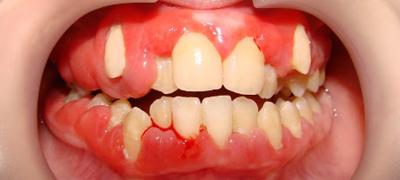

- покраснение и отек в области воспаления;

- покраснение тканей возле очага воспаления.

В самом начале воспалительного процесса болевые ощущения возникают только при надавливании на опухший участок десны. Дальше отек увеличивается, распространяется на губы, щеки или под глаза, в десне образуется гнойник. В это время боли усиливаются и возникают самопроизвольно. Часто происходит расшатывание и разрушение зуба в зоне поражения и повышается температура тела.